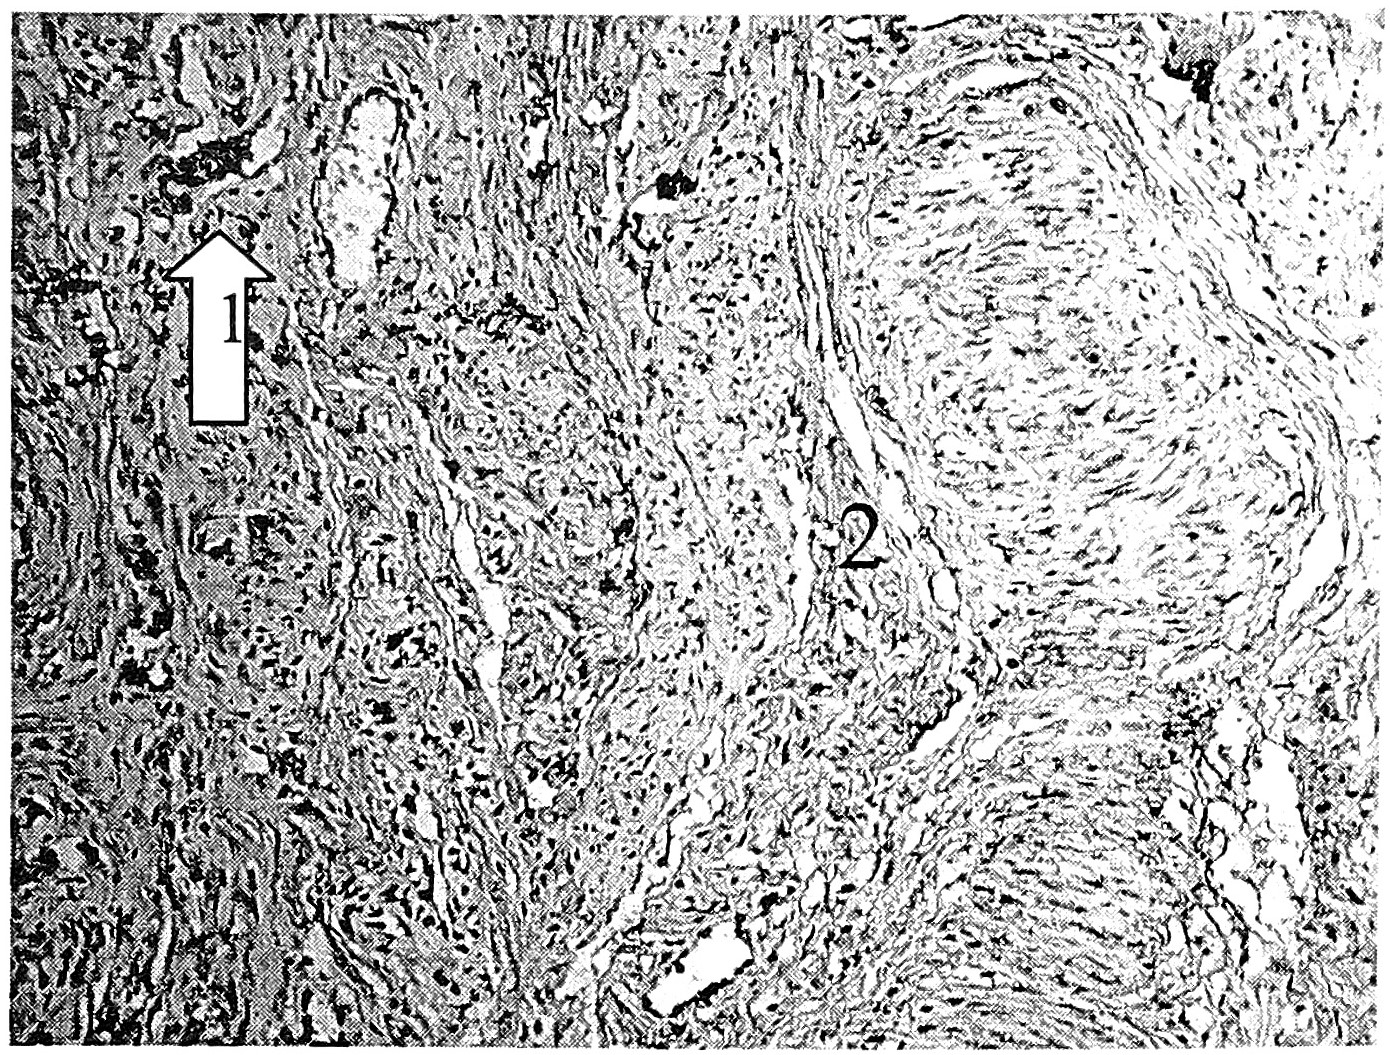

Рис. 3. ЭШМ I степени, ДСТ умеренной степени (пациентка 39 лет). Выраженная экспрессия коллагена III в межмышечной (1) и внутримышечной соединительной ткани (2). Ув. 400.

Характерно относительное снижение экспрессии антител к коллагену I типа в строме, стенках сосудов и повышение ее в пучках мышечных волокон и вокруг лейомиоцитов. В этих же структурах, как в поверхностных, так и в глубоких отделах шейки матки, повышаются и имеют распространенный характер экспрессируемые коллагены III и IV типов (рис. 1, 2, 3).

Сопоставление результатов гистологического и иммуногистохимического исследований позволяет установить топографическую и морфологическую связь между экспрессией показателей коллагенопластики и коллагенизацией аргирофильных волокон в стенках сосудов, вокруг и внутри пучков мышечной ткани, между мышечными волокнами.

Это существенно отличает коллагенообразование при наличии ДСТ от характеристики соединительной ткани в норме. Как известно, для плотной соединительнотканной опорной стромы характерно значительное преобладание коллагена I типа, тогда как в стенках сосудов, в мышечных пучках, вокруг миоцитов имеется коллаген III, IV типов [25, 28].